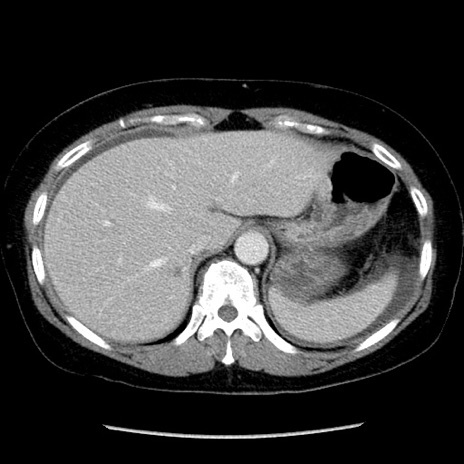

冠状断像

矢状断像